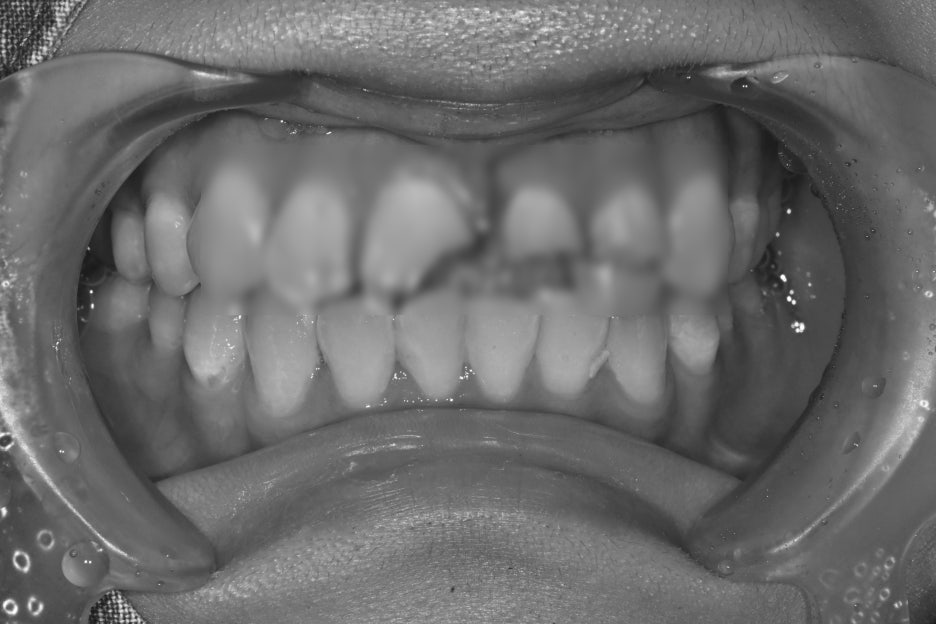

치료 전 후 사진

치료전, 치료후 사진